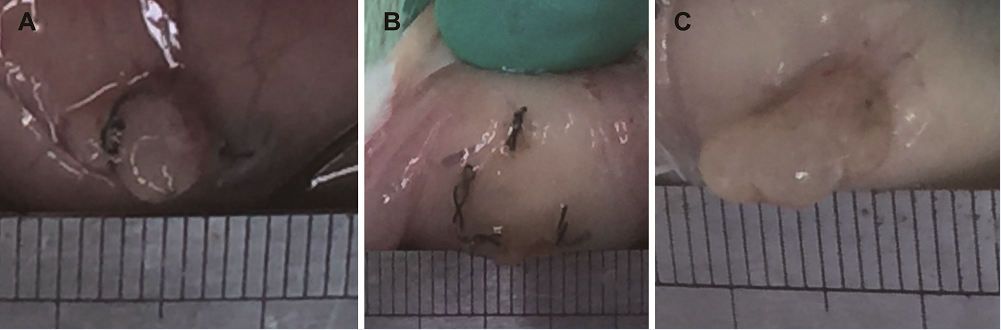

In the first operation, a 3-cm incision was in the midline of the abdomen, and the abdominal cavity was opened. We identified the right uterine horn (approximately 2.0 cm) and tied the mesentery with a 4-0 absorbable suture. After the blood vessels were cut off, we placed the uterine tissue into 0.9% normal saline and cut them into two 1.0 × 0.5 cm sections (Figure 1A). The endometrial surface was attached to the peritoneum and two sections were sutured to the peritoneum of the lower abdominal cavity on both sides using silk thread, as close as possible to an area rich in blood vessels. The abdomen was then closed with 4-0 absorbable suture (Figure 1B). To reduce environmental impact and tissue drying, operation times were limited to 15 minutes. All rats were housed for 2 weeks after the first operation. During this time, all rats were housed and fed as indicated above but none of them were given any medication.

Figure 1.

Figure 1.— Construction of rat endometriosis model by endometrial transplantation. (A) Macroscopic features of transplanted endometrium. (B) Autologous endometrium transplanted on the abdominal wall of rat. (C) Endometriotic lesion formed after 2 weeks of transplantation.

At the end of the 2 week treatment period, rats in the two experimental groups had a second laparotomy performed after a lethal dose of 50% chloral hydrate. Intra-abdominal endometriotic lesions obtained from the vitamin C group and the control group were evaluated (Table 2, Figure 3 and Figure 4). The lesion size of the abdominal wall of each rat was measured by a uniform scale of length × width × height (cm), thus resulting in 14 sets of data obtained from each group of rats. After removal of the lesion, selected portions of these tissues were randomly taken and stored in 10% formaldehyde solution for histopathological examination. The remaining tissues were preserved in liquid nitrogen.

Figure 3.

Figure 3.— Size comparison of endometriotic lesions between vitamin C and control groups. (A and B) Representative endometriotic lesion of vitamin C group. (C) Representative endometriotic lesion of control group.

We measured no significant difference in body weight between rats in the vitamin C group and the control group (Table 1). However, intra-abdominal lesions in the abdominal wall of rats were reduced after intraperitoneal infusion of vitamin C solution compared with controls. In the vitamin C group, no abnormal endometriotic lesions were found in the abdominal wall of one of the rats following the second operation. There were also no observable endometriotic lesions on one side of the abdominal wall in another vitamin C-treated rat. Tabulated lesion volume of the vitamin C and control groups of is shown in Table 2, as well as Figures 3 and 4.